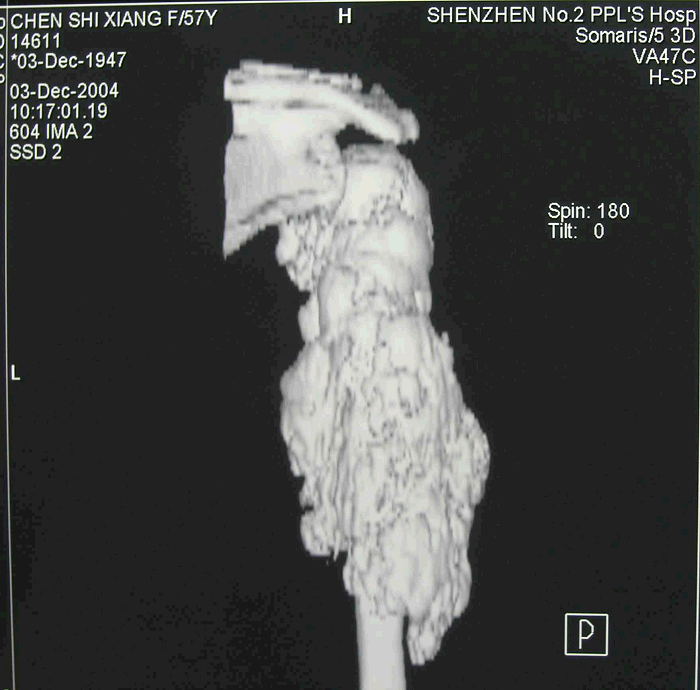

4、病例4:女 58岁 右肱骨中上段髓内高分化骨肉瘤,行瘤段广泛切除异体半关节移植术

图 23 术前CT三维重建象